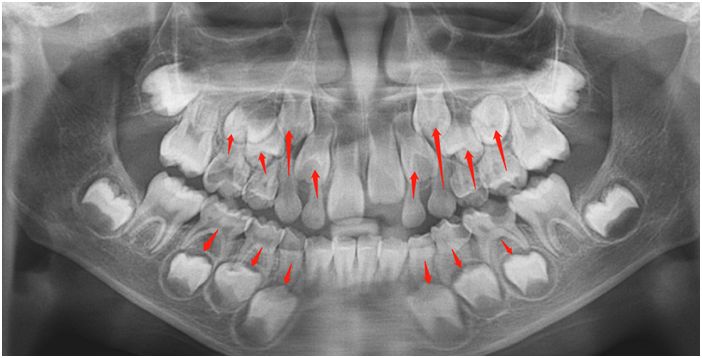

(上图为5岁和11岁小孩口内X线片的对比:绿色的为乳牙,橘红色的为恒牙,数字6为六龄齿)